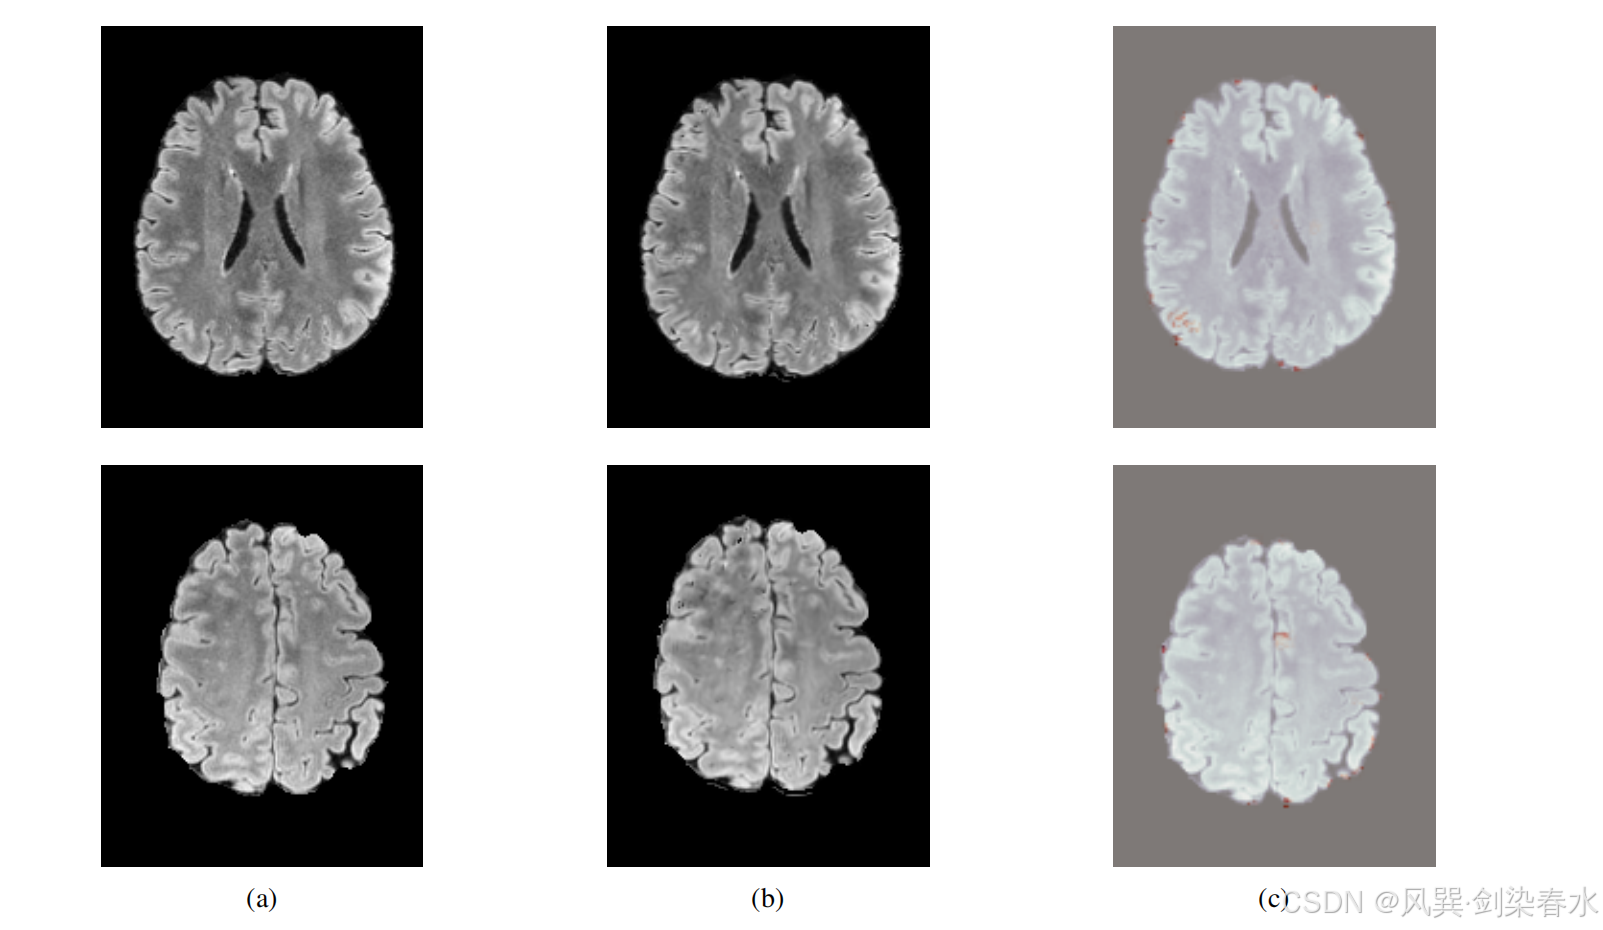

Figure 6 | 来自 BraTS 2021 的健康输入图像(a)、通过 Dif-fuse 生成的图像(b)以及异常图(c):可以观察到,本文的方法能够很好地重建健康样本;